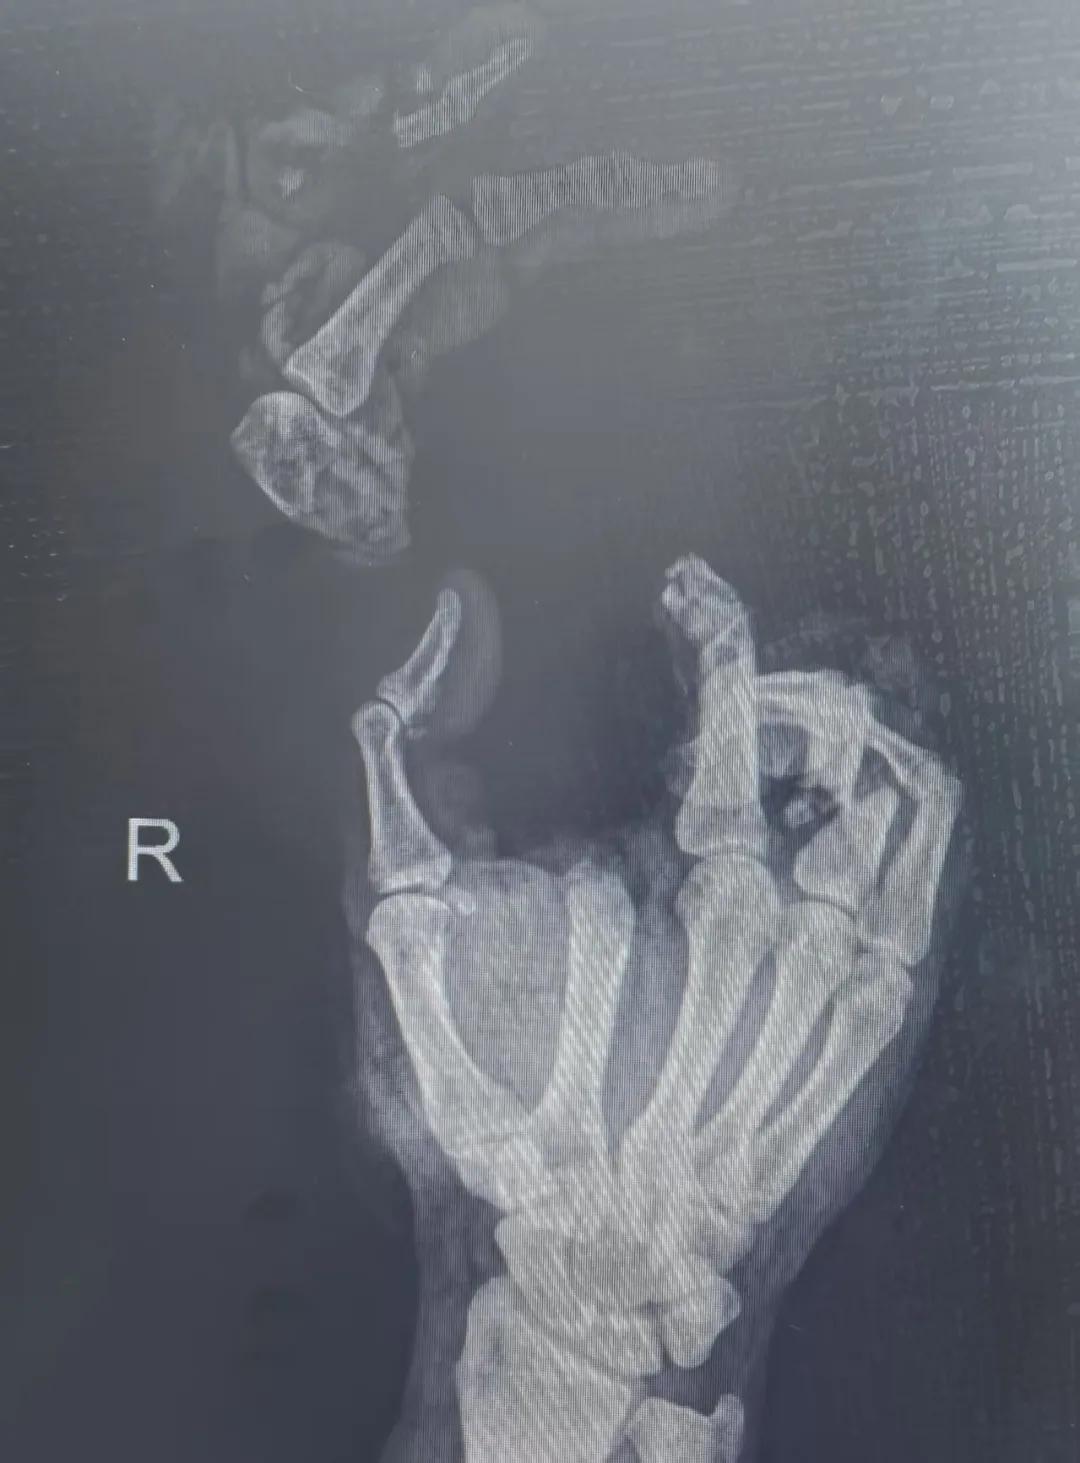

5月20日,市二院顯微外科燒傷整形科收治了3例因麥?zhǔn)毡晦r(nóng)機(jī)“咬傷”、農(nóng)具劃傷的患者。其中,56歲的劉某在收麥子時(shí)被打谷機(jī)皮帶絞傷右手,致手掌、食指、中指、環(huán)指嚴(yán)重毀損傷,骨、關(guān)節(jié)外露,因當(dāng)?shù)蒯t(yī)院無法治療,被家人緊急送往市二院顯微手足燒傷整形外科救治。“當(dāng)時(shí)整個(gè)右手血肉模糊,看上去都是爛的,我以為這個(gè)手是肯定保不住了。”患者家屬回憶當(dāng)時(shí)的場景仍然膽戰(zhàn)心驚。

患者入院后,經(jīng)X線檢查及創(chuàng)面檢查,醫(yī)生診斷為右手食指、中指及環(huán)指旋轉(zhuǎn)撕脫性離斷。接診的顯微手足燒傷整形外科醫(yī)護(hù)人員立即完善了各項(xiàng)術(shù)前準(zhǔn)備,并安排急診手術(shù)。因創(chuàng)面污染嚴(yán)重以及離斷肢體損傷程度較重,手術(shù)歷時(shí)近10小時(shí)。在沈衛(wèi)軍主任的帶領(lǐng)下,科室團(tuán)隊(duì)成功為其進(jìn)行了創(chuàng)面擴(kuò)創(chuàng)、斷肢再植術(shù),術(shù)后患指血運(yùn)良好,在進(jìn)一步觀察治療中。